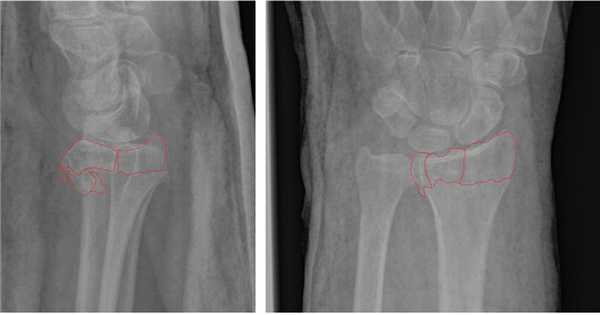

Рис. 1. Внутрисуставной нестабильный перелом лучевой кости.

Рис. 2. . тот же перелом после закрытой репозиции (полного сопоставления отломков нет).

Намного более отчётливо степень нестабильности этих костных фрагментов видна под ЭОП-ом при выполнении функциональных проб. При тыльном сгибании определяется значительное количество мелких фрагментов тыльной кортикальной пластинки и внутрисуставной, оскольчатый характер перелома.